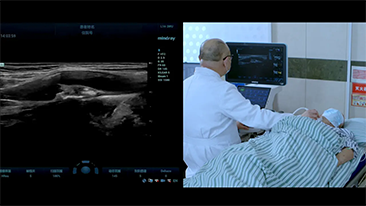

COVID-19: un tiempo desafiante para las personas y los dispositivos

Como consecuencia de la COVID-19, los hospitales y el personal mĂ©dico han desarrollado nuevas prĂĄcticas de trabajo que implican, en los entornos crĂticos, el distanciamiento social, el uso estricto de equipos de protecciĂłn personal (EPP), el lavado de manos y la desinfecciĂłn del equipo todos los dĂas. Los equipos portĂĄtiles altamente mĂłviles y versĂĄtiles pasaron a primer plano en los puntos de atenciĂłn (POC), especialmente cuando las salas y los quirĂłfanos estĂĄn distribuidos en varias plantas y el acceso a los dispositivos especializados es un bien escaso.